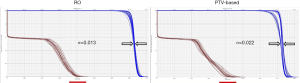

Figure 2 is the DVH for the same lung cancer case. The tables show all range and setup uncertainties for the CTV and spinal cord in the RO plan and the PTV-based plan. The solid lines are the DVHs for the nominal dose distribution which considers no uncertainties appeared. The dashed lines are the DVHs which are concerning different combination scenarios of range and setup uncertainties. By simply comparing the bandwidth in DVH at 50% of the targets compared to PTV-based optimization, we were able to quickly evaluate the plan robustness in defiance of uncertainties. In the figure, it is noticeable that the DVH bands in CTV are narrower for the RO than PTV-based plan. The CTV bandwidth were 0.76 Gy (RBE) in RO, and 3.78 Gy (RBE) in PTV-based optimization. Moreover, the falloff slope of the DVH bands in CTV was steeper, and the maximum dose of spinal cord was lower in the RO plan than PTV-based plan.

Besides from bandwidth comparison, we also used the following equation to calculate a sigma value (σ) so to quantify the distribution of DVH bandwidths in targets for each plan for robustness evaluation. If sigma value is smaller, it indicates the plans has less sensitivity to range and setup uncertainties.

σ=(

The outcome of sigma-value evaluation showed the RO plan was less sensitivity to the uncertainties by reducing sigma-value of 0.008 on average, and dose sparing on critical organs was not compromised.

Figure 3 and Figure 4 show the transverse dose distribution and DVH for one head-and-neck case. The dose distribution in the RO plan was insensitive to range and setup uncertainties compared to PTV-based plan. The DVH bands of target was narrower for the RO than PTV-based plan. The sigma value was also smaller which indicates the plan has less response to proton uncertainties. Both the head-and-neck and lung cases showed similar results.

In the dose comparison results for the same lung and head-and-neck cases above, we observed RO led to a slight better target-dose coverage than PTV-based optimization by increasing D95% of CTV about 1.5 Gy (RBE) on average [1.1–1.9 Gy (RBE)], and provide more homogeneous dose distributions by improving HI (D5%/D95%) about 0.03 to 0.04. However, we did not see the significant dose changes on critical organs and the dose difference were mostly within 3 Gy (RBE) between RO and PTV-based plans.

For the other lung and head-and-neck cases both presented similar outcome. The sigma values of CTV were 0.007 [RO], and 0.014 [PTV-based] for the second lung case. For head-and-neck case, the sigma values were 0.018 [RO], and 0.021 [PTV-based]. No significant dose changes on critical organs were observed.